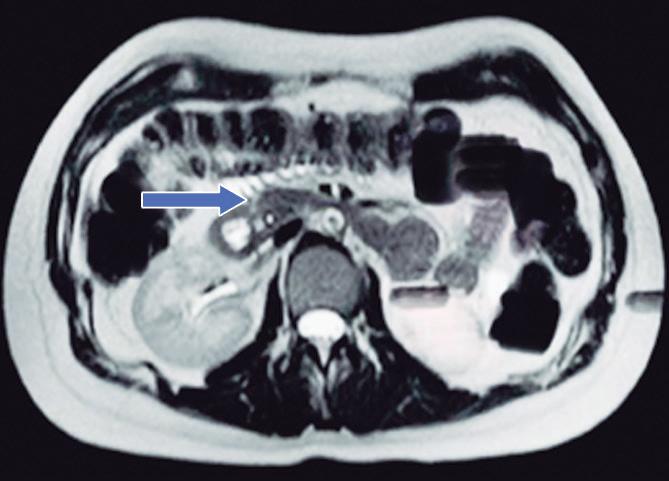

Consiste en una anomalía de la migración del brote pancreático ventral, el cual no rota o lo hace de manera incompleta, resultando en la presencia de tejido glandular pancreático a la derecha del duodeno, rodeando a su 2° porción (Figura 8). Han sido descriptos dos subtipos: el extramural, donde el conducto de Wirsung rodea al duodeno uniéndose al conducto pancreático principal; y el intramural, donde el tejido pancreático se entremezcla con la pared duodenal y sus secreciones drenan directamente a la luz a través de conductos muy pequeños.16

En las imágenes encontramos parénquima pancreático rodeando a la 2° porción duodenal, habitualmente en toda su circunferencia y en ocasiones de manera incompleta. En la colangio-RM es posible visualizar al conducto pancreático a la derecha del duodeno, con un recorrido que se dirige a la ubicación de la papila mayor (Figura 9).17

A) Resonancia magnética secuencia T1 con gadolinio, plano axial. Las flechas señalan el parénquima del páncreas prolongado hacia la derecha “abrazando” a la 2° porción duodenal (cabeza de flecha). B) Resonancia magnética, secuencia T1 con gadolinio, plano axial, corte más caudal al previo. Las flechas nos muestran al páncreas rodeando de manera completa a la 2° porción del duodeno. C) Resonancia magnética, secuencia T2, plano coronal. La flecha señala presencia de parénquima glandular y conducto pancreático a la derecha del duodeno (cabezas de flecha). D) Resonancia magnética, secuencia T2, plano coronal, corte posterior al previo. El páncreas anular y su conducto de drenaje rodean en forma completa al duodeno (cabezas de flecha). E) Colangio-RM. El conducto del páncreas ventral (flechas) hace un giro, rodea al duodeno (cabeza de flecha) y se une al conducto pancreático principal para drenar en la papila mayor. F) Colangio-RM. La imagen magnificada muestra con mayor detalle el recorrido del conducto de Wirsung en el contexto de un páncreas anular.